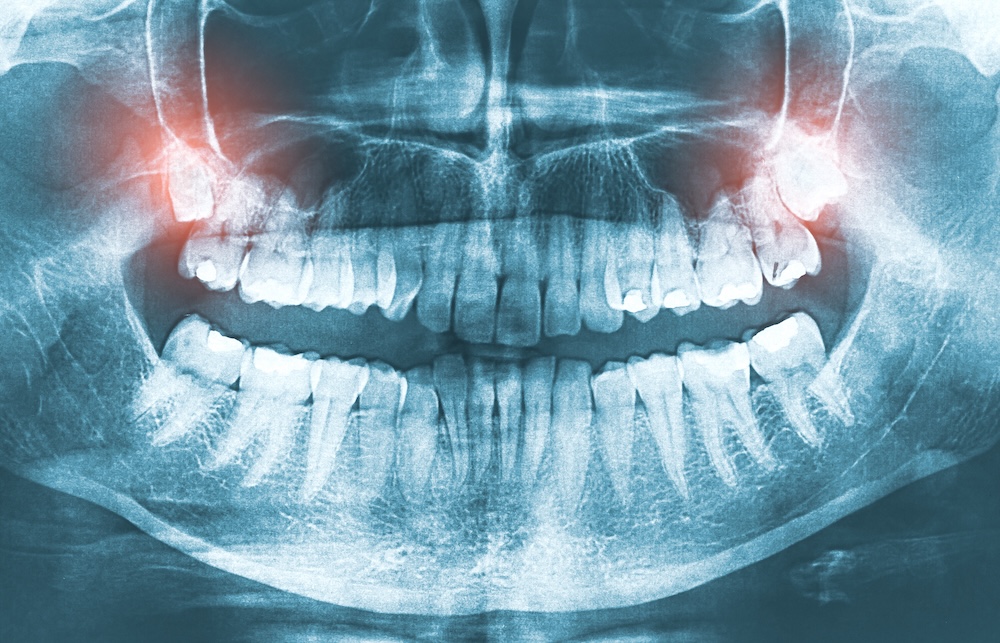

Wisdom teeth usually erupt (grow in) between the ages of 17 and 25. But keep in mind, you might not see wisdom teeth when you look in your mouth, especially if they're fully impacted.

Impaction: When there's insufficient space in the jaw, wisdom teeth may become trapped beneath the gum line, leading to pain and potential infection.

Infection and Inflammation: Partially erupted wisdom teeth can create pockets that trap food and bacteria, increasing the risk of infections and gum disease.

Crowding: Wisdom teeth can push against neighboring teeth, potentially causing misalignment or undoing previous orthodontic work.

The decision to remove wisdom teeth varies among individuals. If they are properly aligned, fully erupted, and don't cause any problems, the wisdom teeth may remain in place without problems. However, a partial eruption of the wisdom teeth allows an opening for bacteria to enter around the tooth and cause an infection, which results in pain, swelling, jaw stiffness, and general illness. Partially erupted teeth are also more prone to tooth decay and gum disease, because their hard-to-reach location and awkward positioning makes brushing and flossing difficult. This can cause pain, infection, or lead to impaction or crowding, and removal may be recommended. It's essential to consult with your dentist who will evaluate all the information about your condition to determine the best course of action based on your specific situation.